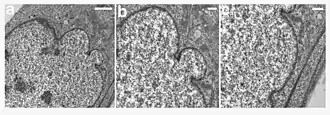

![]() | |

| A young girl with progeria (left). A healthy cell nucleus (right, top) and a progeric cell nucleus (right, bottom). | |